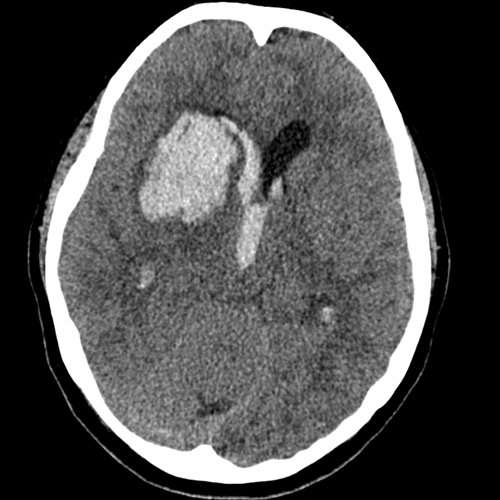

La utilización de la tomografía computarizada sin contraste o la resonancia magnética con secuencias de susceptibilidad magnética, como la imagen por eco de gradiente, es fundamental en el contexto de la hemorragia intracerebral. Estos métodos de imagen no solo permiten confirmar la presencia de hemorragia, sino que también son cruciales para determinar el tamaño y la ubicación del hematoma, lo cual tiene implicaciones directas en el manejo clínico y pronóstico del paciente.

La tomografía computarizada es particularmente valiosa en las primeras horas tras el evento hemorrágico, ya que proporciona imágenes rápidas y efectivas que pueden identificar hematomas agudos. La resonancia magnética, por su parte, ofrece un contraste más detallado de los tejidos y puede detectar cambios sutiles en la morfología cerebral y en la dinámica de la hemorragia.